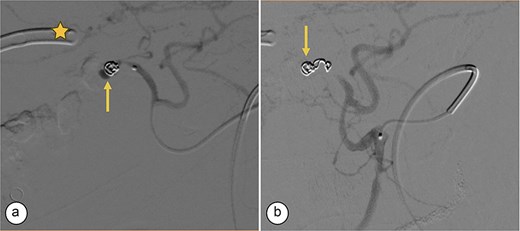

Surgical reconstruction revealed an excluded PRHD and ARHD–LHD continuity with obstruction 10 mm from the confluence. The PRHD catheter was found outside the biliary tract, so a transhepatic Nelaton catheter was placed from inside to out. A neoconfluence of PRHD with ARHD and LHD was created with a 30 mm hepaticojejunostomy. A transanastomotic Nelaton catheter and a supranastomotic ARHD catheter were left in place. Estimated blood loss: 300 cc. In the immediate postoperative period, the patient developed melena and bleeding from the Penrose drain. Cholangiography via the right percutaneous catheter showed no contrast leakage. Angio-CT revealed an 8 × 5 mm saccular lesion in the anterior right hepatic artery (Segment V), consistent with a pseudoaneurysm (Figs 1 and 2). Selective embolization with three microcoils (2 × 3 × 2.3 mm) was successfully performed (Fig. 3). The patient had a favorable recovery, with no further bleeding, and was discharged in stable condition for outpatient follow-up. Control imaging of the ARHD catheter confirmed adequate visualization of all hepatic ducts, allowing catheter removal (Fig. 4).

Supranastomotic percutaneous transcatheter cholangiography. Hepaticojejunostomy (arrowhead), microcoils (arrow), and percutaneous catheter (star).